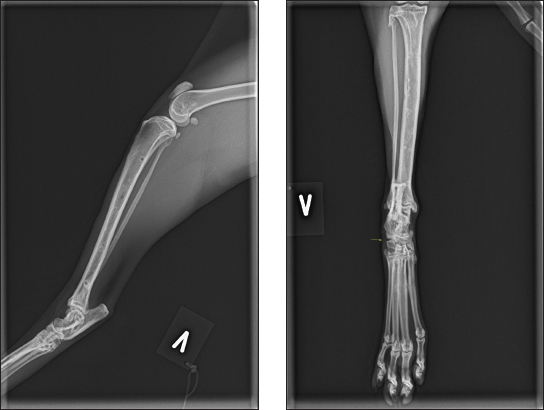

Palpation of the affected leg revealed noticeable swelling and discontinuity of the hook joint. The fracture was closed, and orthogonal radiographs revealed a dislocated talar neck fracture, with tibiotalar and subtalar luxation (Fig. 1a and 1b). Based on the nature of the fracture, it was anticipated that there would be collateral support disruption.

Fig. 1. (A and B) Mediolateral and craniocaudal digital radiography of the left hock joint. The talar neck fracture is evident, with luxation of both the tibiotalar and subtalar joints.